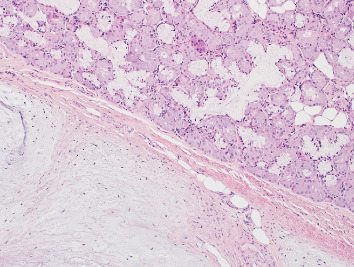

目的:本病例报告描述了一个罕见的扁桃体窝内的口腔软骨绒毛瘤,强调了识别和区分这种不常见的实体与更常见的口腔病变的重要性。方法:对一位30岁男性患者进行了全面的临床和组织病理学检查,他表现为鼻咽部无痛性肿块。进行了切除活检,并进行了组织病理学分析,以建立明确的诊断。结果:组织病理学检查显示为软骨性脉络瘤,其特征是结缔组织包围着成熟的透明软骨。患者接受手术切除病变,随访评估显示良好的术后结果,无复发。结论:口腔软骨脉络膜瘤极为罕见。意识到这个实体是至关重要的准确诊断和适当的管理,因为它可以模仿其他更常见的口腔病变。本病例报告补充了关于口腔软骨脉络瘤的有限文献,并强调了在口腔粘膜肿块鉴别诊断中考虑这一实体的重要性。

Objective: This case report describes a rare presentation of a cartilaginous choristoma of the oral cavity within the tonsillar fossa, emphasizing the importance of recognizing and differentiating this uncommon entity from more frequently encountered oral lesions. Methods: A comprehensive clinical and histopathological examination was conducted on a 30-year-old male patient who presented with a painless mass in the nasopharynx. An excisional biopsy was carried out, and a histopathological analysis was conducted to establish a definitive diagnosis. Results: Histopathological examination demonstrated a cartilaginous choristoma, characterized by the presence of mature hyaline cartilage surrounded by the connective tissue. The patient underwent surgical excision of the lesion, and follow-up assessments indicated a favorable postoperative outcome without recurrence. Conclusion: Cartilaginous choristomas in the oral cavity are exceedingly rare. Awareness of this entity is crucial for accurate diagnosis and appropriate management, as it can mimic other more common oral lesions. This case report contributes to the limited literature on oral cartilaginous choristomas and underscores the significance of considering this entity in the differential diagnosis of oral mucosal masses.